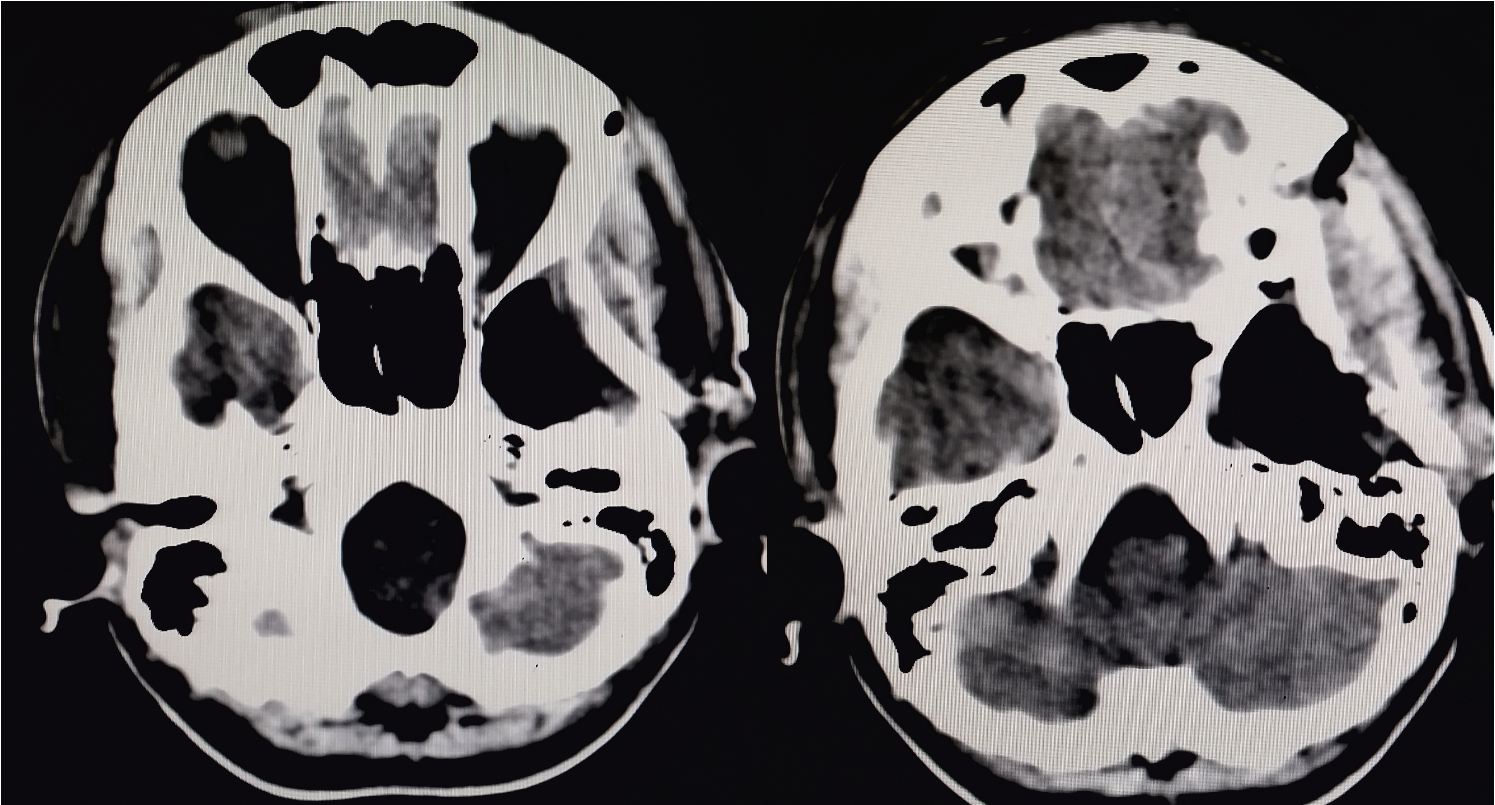

Далее представлены данные контрольной спиральной компьютерной томографии (СКТ) головного мозга больной на 1-е сутки после операции (видно скопление воздуха в зоне резекции медио- базальных отделов левой височной доли, дренажная трубка эпидурально) (рис. 5).

Рис. 5. СКТ головного мозга на 1-е сутки после передней височной лобэктомии и амигдалгип- покампэктомии слева